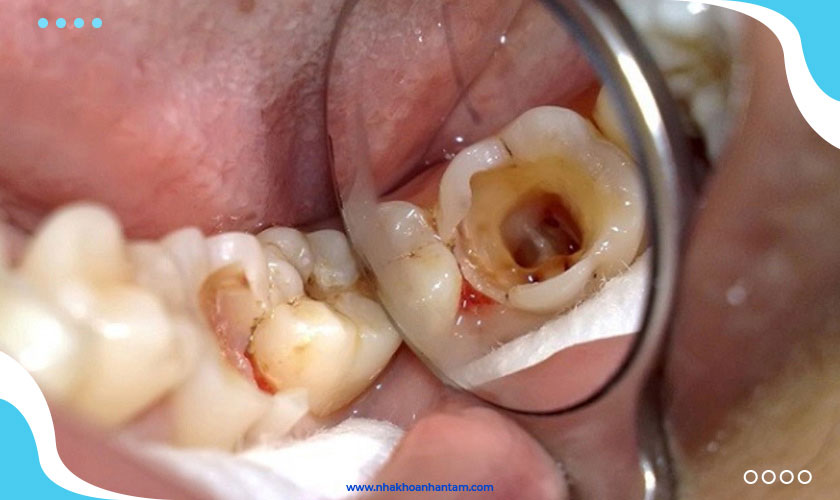

Răng sâu nặng thường không tránh khỏi trường hợp phải lấy tủy vì mô răng sâu sẽ gây ảnh hưởng đến tủy răng. Muốn lấy sạch phần mô răng sâu này không thể không tác động đến tủy răng. Bởi vậy, cần phải thực hiện đồng thời việc nạo mô răng sâu với chữa tủy. Sau đó mới thực hiện trám răng để phôi phục lại hình thể răng, bù đắp lượng mô răng thật đã mất để răng thực hiện được chức năng ăn nhai bình thường.

Răng sâu nặng thường không tránh khỏi trường hợp phải lấy tủy

Chỉ trong những trường hợp răng chớm sâu hoặc sâu răng nhẹ mới tránh được việc trám răng lấy tủy. Bạn chỉ cần nạo đi một lượng nhỏ men răng bị sâu sau đó trám lại là có thể hoàn tất mà không cần tác động đến tủy răng.